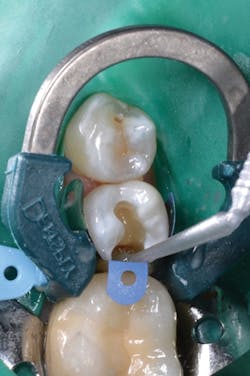

Prime&Bond Elect was generously applied to the entire cavity preparation, and the material was agitated for 20 seconds (figure 3). The excess solvent was removed by gently drying with clean, dry air for at least 5 seconds and light cured for 10 seconds with a dental curing light. The restorative materials were applied to complete the restoration (figure 4).

Figure 3: Prime&Bond Elect was applied to the entire preparation and agitated for 20 seconds.